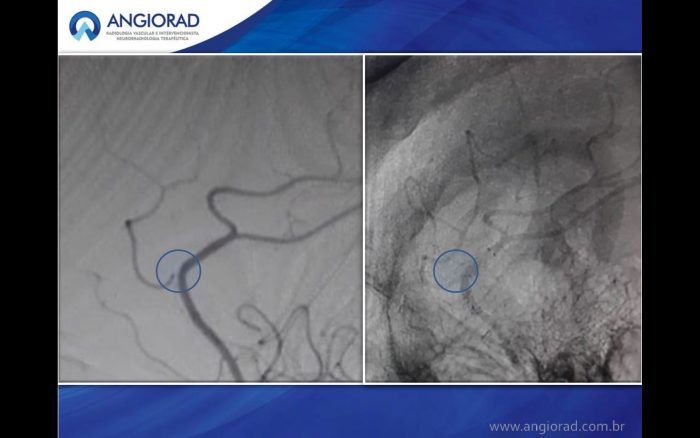

Paciente apresentando aneurisma incidental de colo largo relacionado a artéria pericalosa esquerda durante procedimento de embolização de aneurisma de carótida interna por hemorragia subaracnóide.

O caso descrito apresenta oclusão completa do aneurisma e preservação vascular após controle angiográfico com 6 meses.